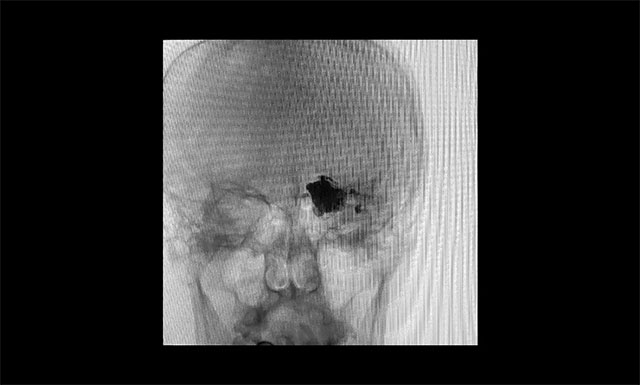

▲术毕铸型